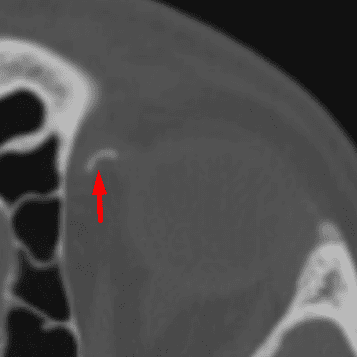

Mendosal Suture

Case 18